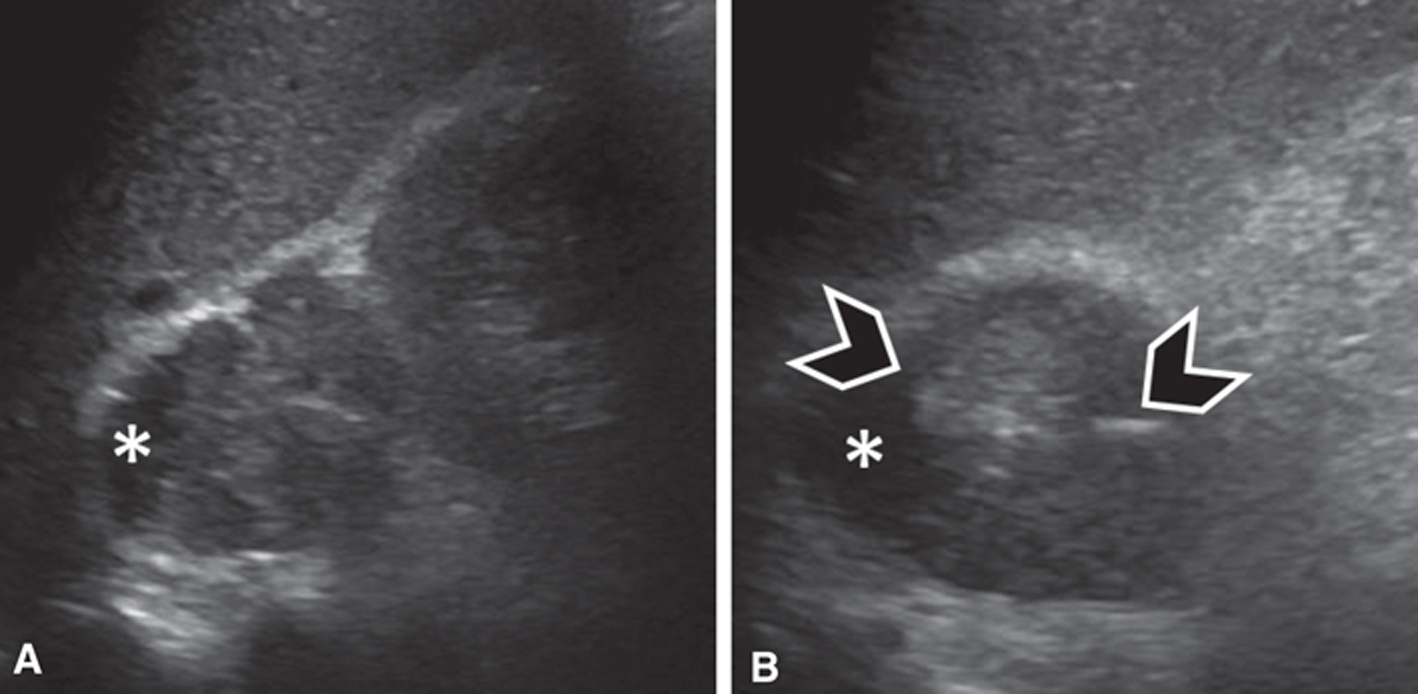

Fig 1

Figure 1 Several neuroendocrine tumors in a 60-year-old male patient with succinate dehydrogenase (SDH) subunit D mutation. (A, B, C) MRI of the abdomen demonstrates two left retroperitoneal lesions, one that is arising from the left adrenal gland (arrowheads) and a larger one more inferiorly, posterior to the fourth segment of the duodenum (white arrows) seen on (A) coronal fat-saturated post-contrast T1-weighted images and (B–C) fast spin echo T2 weighted images. The lesions were surgically resected. The left adrenal lesion was consistent with pheochromocytoma and the more inferior lesions were consistent with paraganglioma. (D) The patient underwent a gallium-68-DOTATATE scan to screen for additional neuroendocrine tumors. This demonstrated intense focal tracer uptake in the right neck (circle). (E) CT angiography and MRI of the neck (not shown) were performed for further characterization and the lesion (black arrow) was consistent with a glomus vagale paraganglioma.